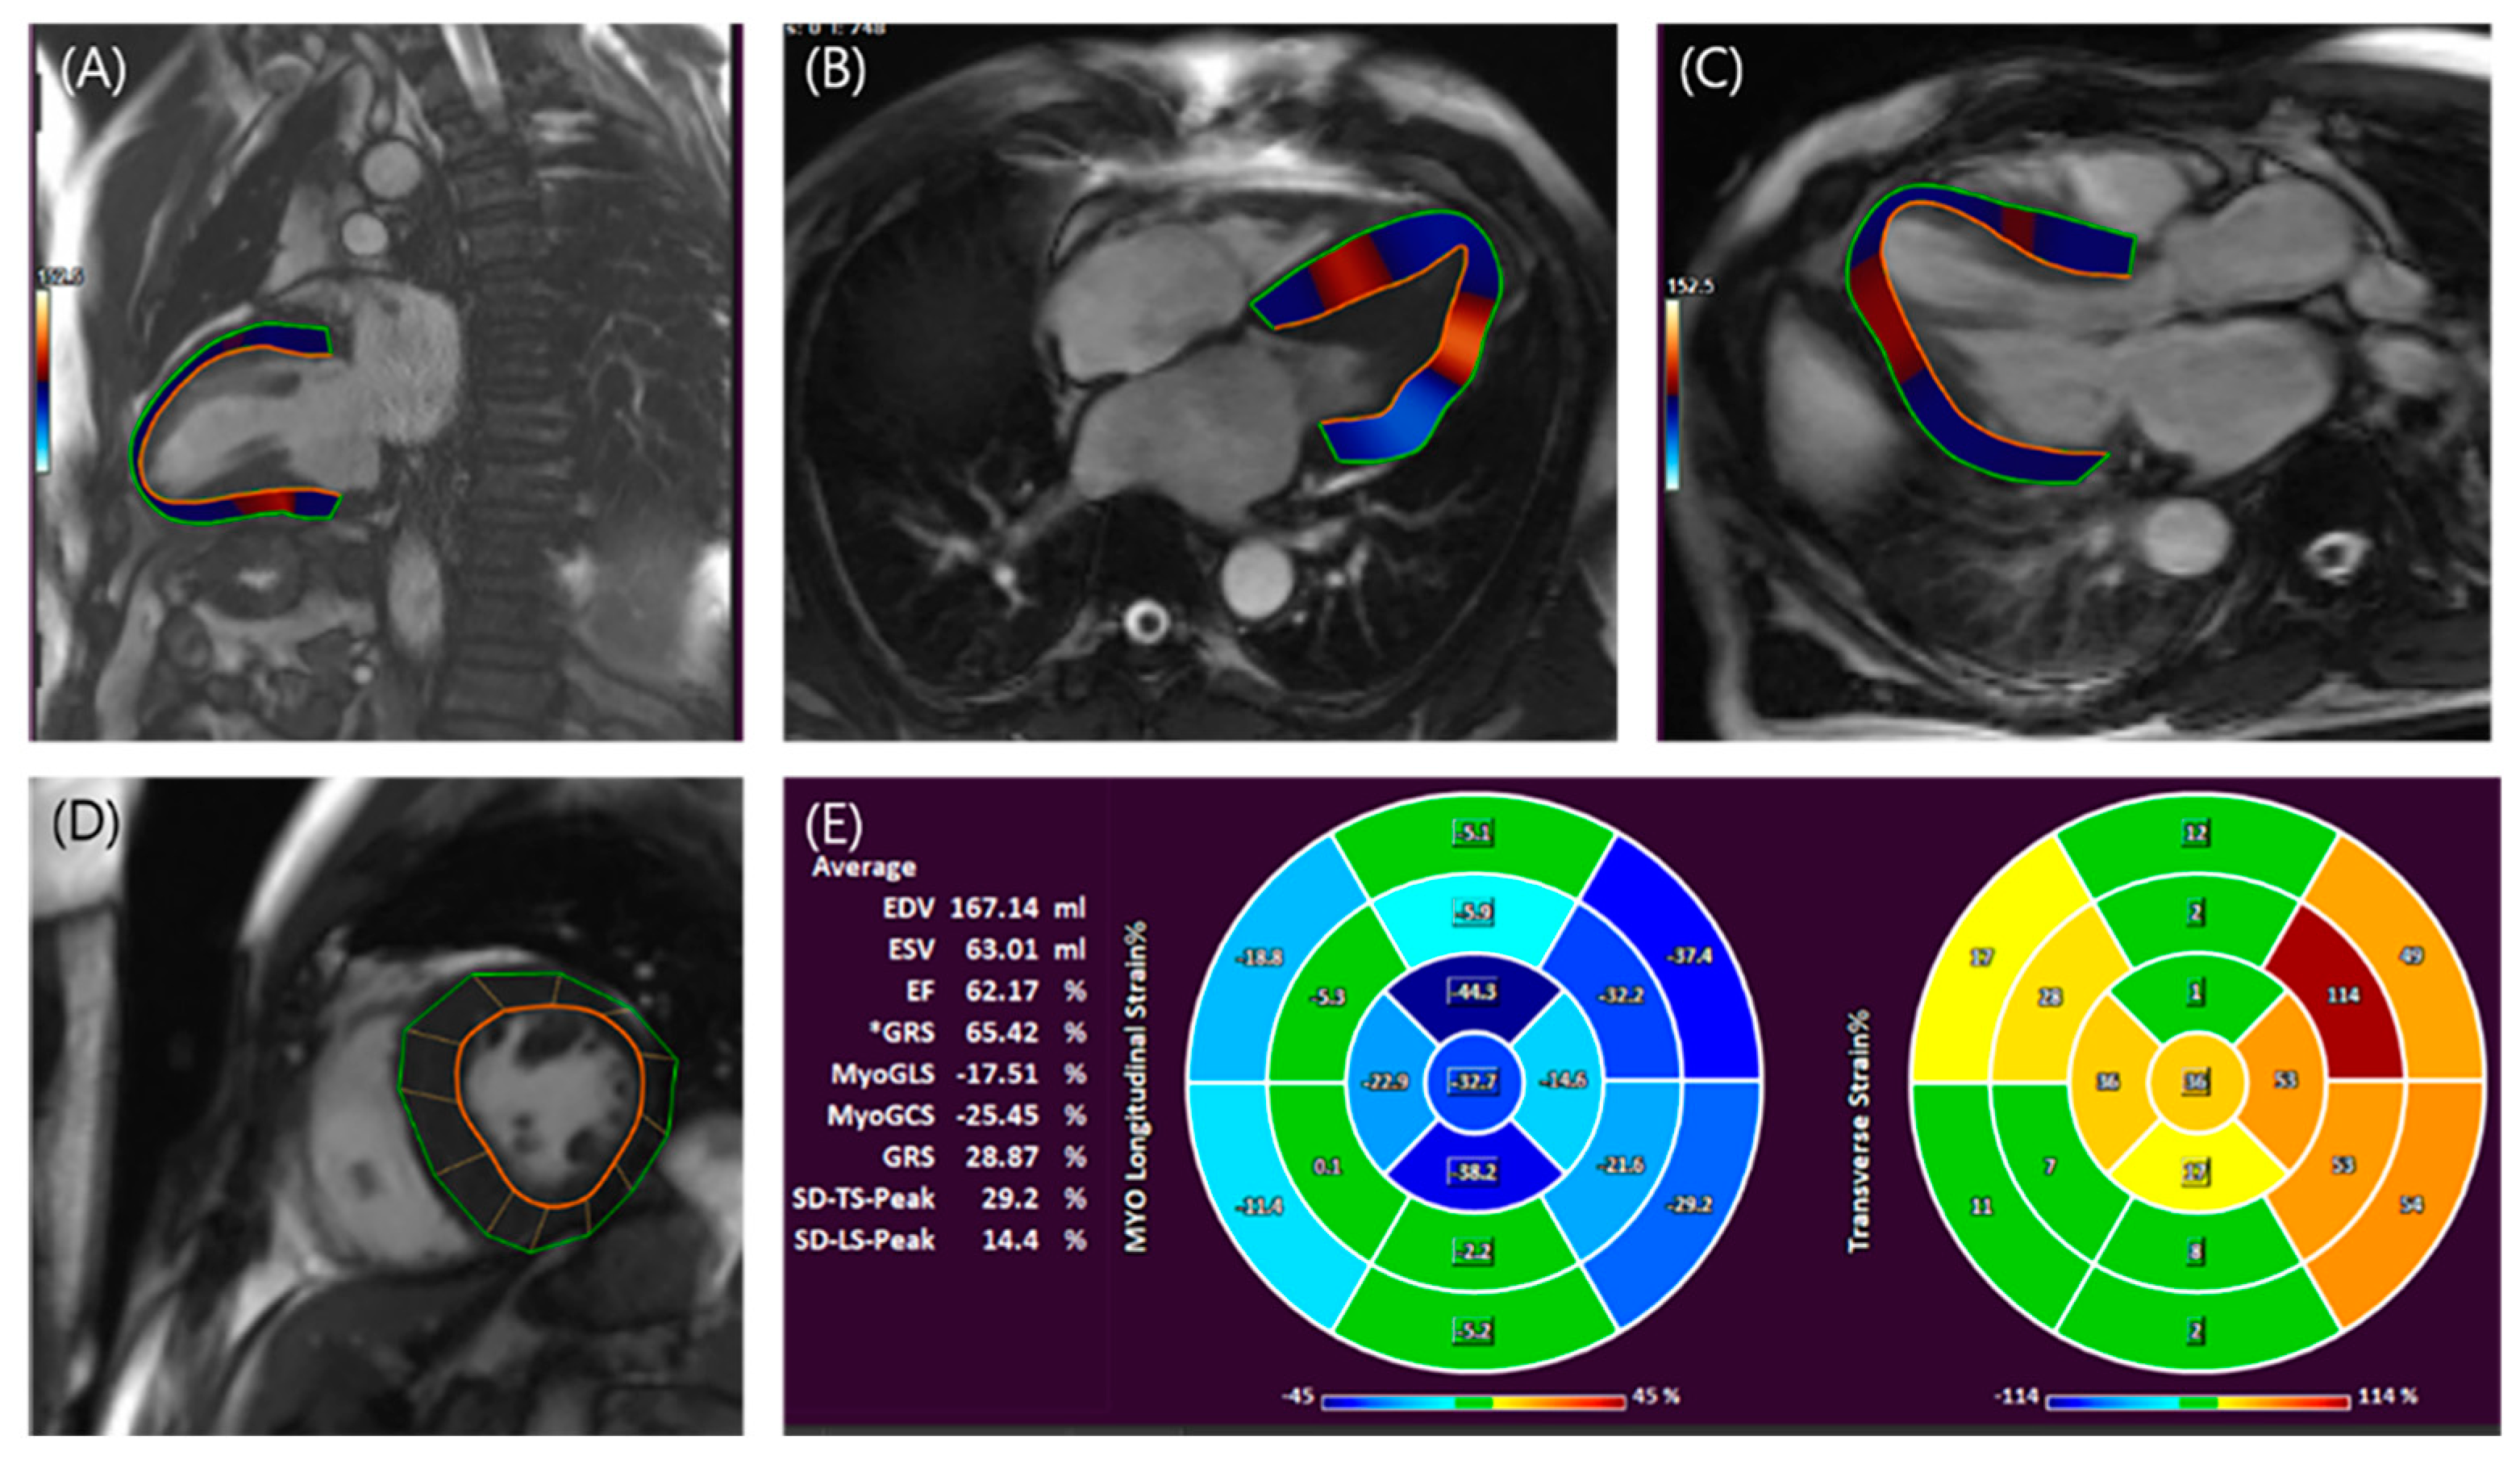

- Yang, Y.; Yin, G.; Jiang, Y.; Song, L.; Zhao, S.; Lu, M. Quantification of left atrial function in patients with non-obstructive hypertrophic cardiomyopathy by cardiovascular magnetic resonance feature tracking imaging: A feasibility and reproducibility study. J. Cardiovasc. Magn. Reson. Off. J. Soc. Cardiovasc. Magn. Reson. 2020, 22, 1–11. [Google Scholar] [CrossRef]

- Cavus, E.; Muellerleile, K.; Schellert, S.; Schneider, J.; Tahir, E.; Chevalier, C.; Jahnke, C.; Radunski, U.K.; Adam, G.; Kirchhof, P.; et al. CMR feature tracking strain patterns and their association with circulating cardiac biomarkers in patients with hypertrophic cardiomyopathy. Clin. Res. Cardiol. 2021, 110, 1757–1769. [Google Scholar] [CrossRef]

- Pagourelias, E.D.; Alexandridis, G.M.; Vassilikos, V.P. Fibrosis in hypertrophic cardiomyopathy: Role of novel echo techniques and multi-modality imaging assessment. Heart Fail. Rev. 2021, 26, 1297–1310. [Google Scholar] [CrossRef]

- Wang, J.; Ma, X.; Zhao, K.; Yang, S.; Yang, K.; Yu, S.; Yin, G.; Dong, Z.; Song, Y.; Cui, C.; et al. Association between left atrial myopathy and sarcomere mutation in patients with hypertrophic cardiomyopathy: Insights into left atrial strain by MRI feature tracking. Eur. Radiol. 2023. online ahead of print. [Google Scholar] [CrossRef] [PubMed]